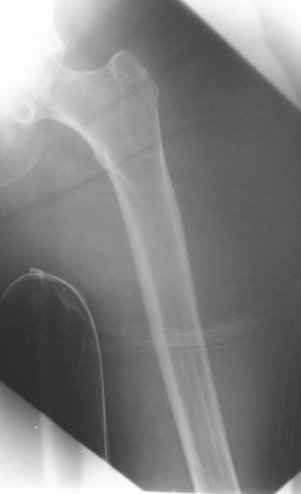

Go antegrade if you have an approriate implant available. Attached is a result of a similar fracture.

My preference would be to rigidly fix the fracture internally. I just feel that it may not be possible given the very porotic nature of the bone distal to the fracture (I am re-sending the lateral x-ray which really concerns me).

I doubt if I could lock a nail (either antegrade or retrograde) distal to the fracture which extends virtually to the implant. I have similar concerns about plate fixation. Has anyone got a reasonable volume of experience with this type of fracture?